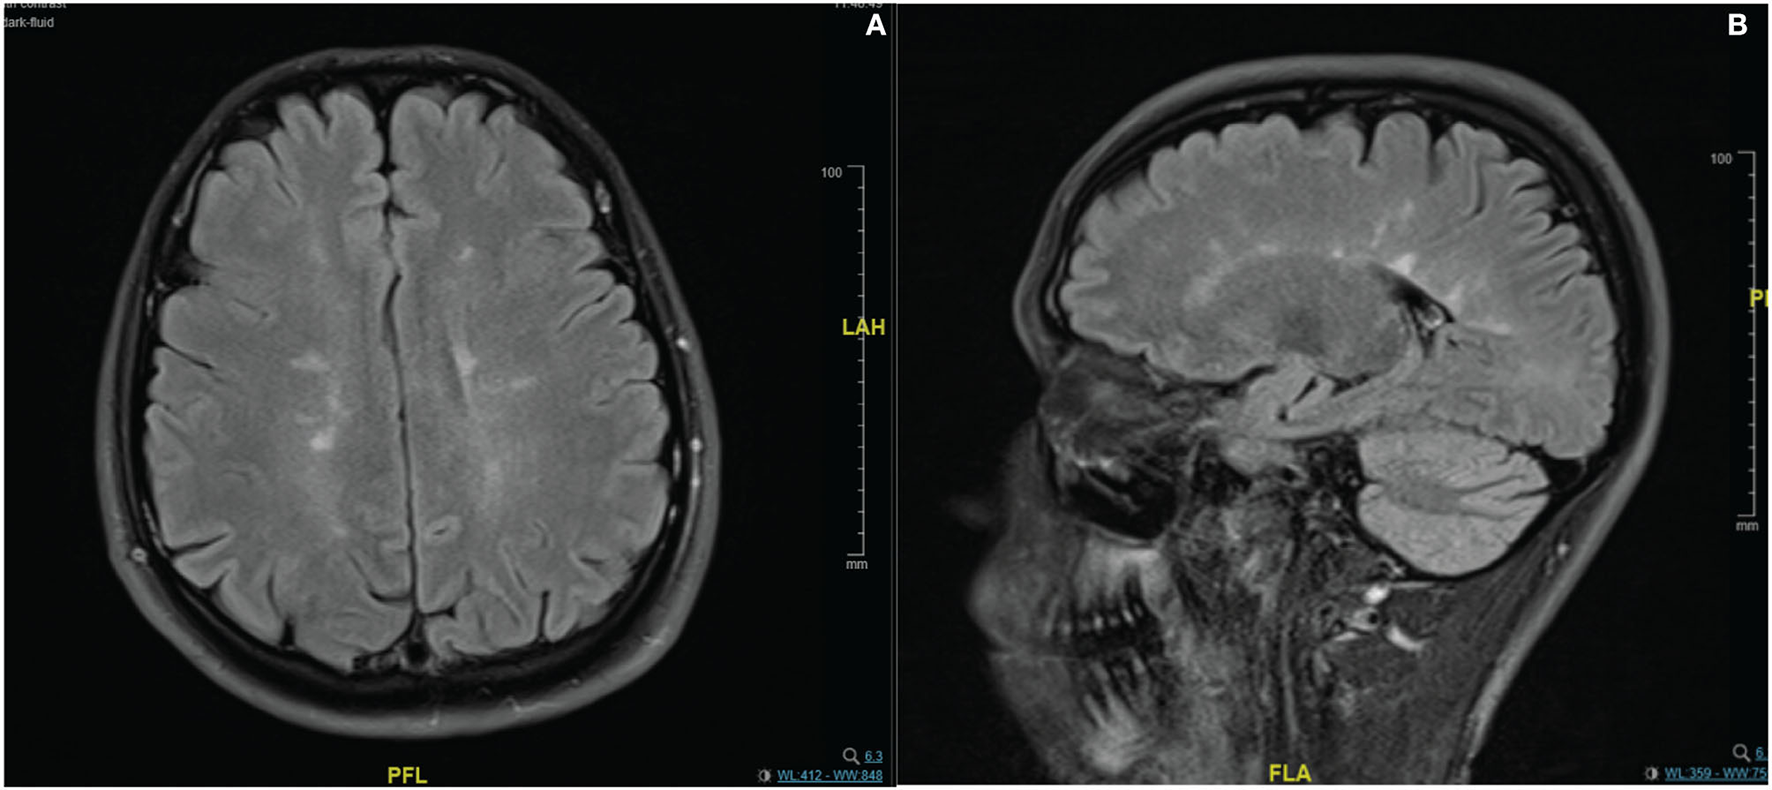

In the imaging, brain MRI with contrast was performed on the day of admission and showed multiple abnormal high signal intensities involving cortical, juxtacortical, subcortical, and periventricular with one lesion at the left anterior aspect of the pons. Additionally, some lesions were perpendicularly oriented to the corpus callosum representing Dawson's fingers (Figure 1). Spinal cord MRI showed multiple abnormal high signal intramedullary lesions at the central, posterior, and lateral aspects of the cervical and thoracic spinal cord (Figure 2). Pan computed tomography (CT) scan and bronchoscopy were also performed and were unremarkable for malignancies.

Figure 1

Contrast enhanced MRI brain imaging on the day of admission. Fluid attenuated inversion recovery (FLAIR) sequence (A,B). Showing multiple abnormal high signal intensities involving cortical, juxtacortical, subcortical, and periventricular regions. Some lesions were perpendicularly oriented to the corpus callosum representing Dawson's fingers.